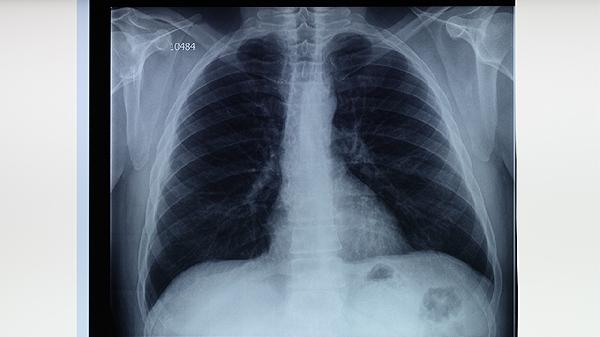

肺结核治愈后是否会在影像学检查中留有痕迹,需结合病灶吸收程度、纤维化程度及钙化情况综合判断。

轻度肺结核经规范治疗后,肺部炎症可完全吸收,胸片或CT可能无异常表现。早期发现并治疗的局限性病灶,6-12个月后影像学检查可能恢复正常。

中重度肺结核治愈后常遗留肺纤维化,CT可见条索状高密度影。这种瘢痕组织与正常肺纹理不同,多分布于肺尖或上叶后段,可能伴随局部胸膜增厚。

结核杆菌被消灭后,坏死组织可能钙化形成高密度结节。胸片可见直径2-10mm的致密影,CT显示更清晰,这种改变终身存在但不影响功能。

严重病例可能继发支气管扩张,CT可见柱状或囊状气道变形。这类结构性改变不可逆,可能伴随反复咳嗽、咯血等症状,需定期随访监测。

结核空洞治愈后可能完全闭合或形成薄壁囊腔。闭合性空洞仅残留星状瘢痕,开放性空洞则持续存在薄壁环形阴影,两者均需与肿瘤性病变鉴别。